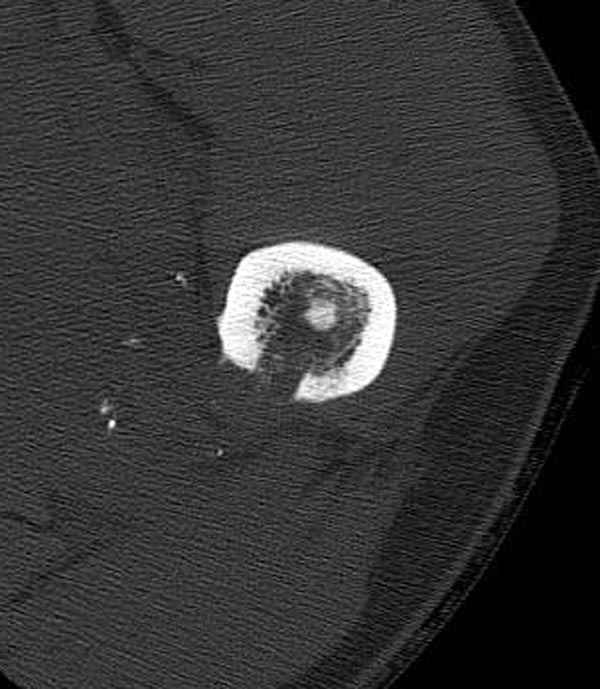

Больной с огнестрельным переломом бедра с вовлечением около 15% медиального кортекса, входное отверстие около 1 см в диаметре; стабильный, без сосудистых и неврологических признаков.

Учитывая, что больной получил травму не во время визита в церковь, и он является одним из представителем 40 миллионного “outstanding itizen”, без медицинской страховки, без работы в свои 39 лет, и без надлежающей ортопедической дисциплины у которого отсутсвует страх стрессового перелома, было рекомендовано оперативное лечение: профилактическое антеградное интрамедуллярное штифтование.

Методика штифтования при отсутствии большой зоны перелома как при онкологических профилактических штифтованиях, расверливание интрамедуллярного канала проводим с предварительным наложением дополнительного дренажного отверстия в дистальном отделе бедра (в данном случаи в канале оставили 6.5 мм канюлированный шуруп), иначе при создании давления в канале во время сверления имеется опасность эмболизации легочной артерии тромбом.